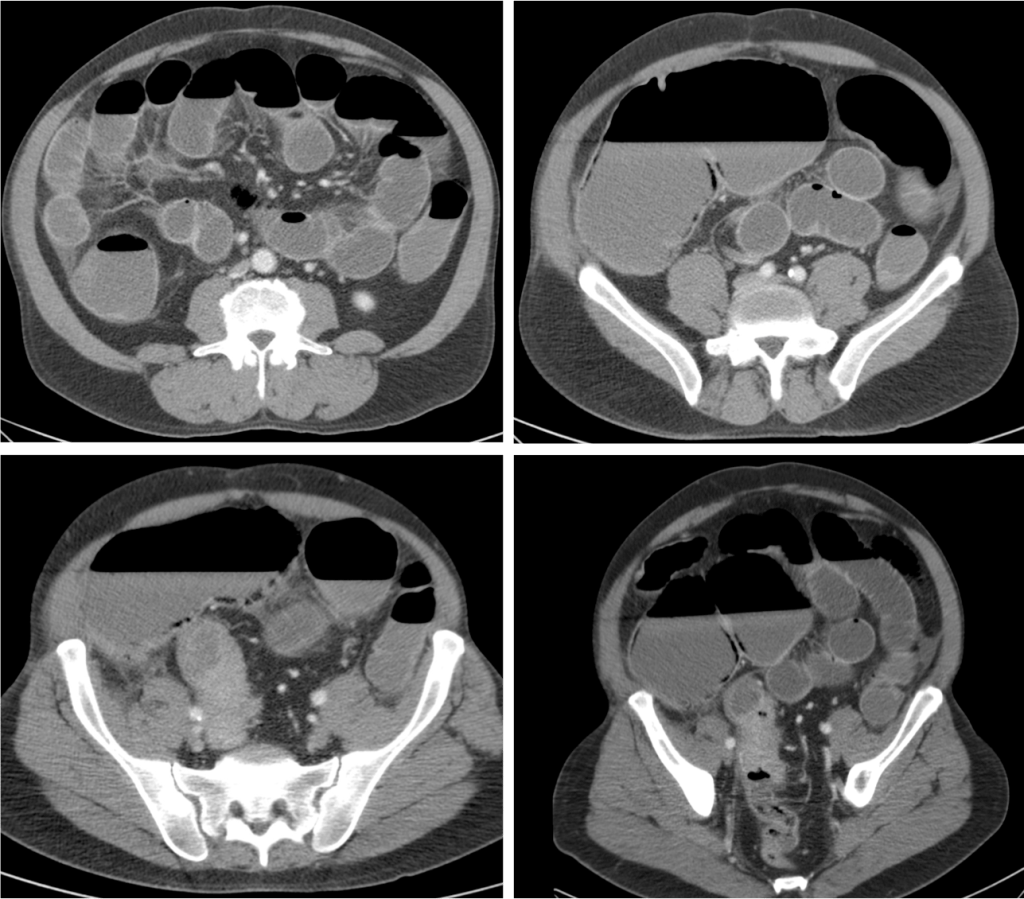

Tomografía Computarizada:

Con sensibilidad y especificidad próximas al 100%, es la técnica inicial de elección ante la sospecha de una obstruccion intestinal. Ante la sospecha firme de obstruccion intestinal, realiza un diagnóstico más preciso, aporta más información adicional y evita retrasos en el diagnóstico.

Hallazgos:

- Distensión proximal a la obstrucción mayor de 3,5 cm en el intestino delgado y mayor de 5 cm en el colon con colapso de asas distales junto con la identificación, siempre que sea posible, de la zona del cambio de calibre (zona de transición), lo que nos permite realizar con mayor seguridad el diagnóstico.

- Si se observan asas dilatadas, independientemente del grado, si no hay colapso de asas distales, el diagnóstico más probable es un íleo paralítico.

- Engrosamiento mural de asas.

- Afectación de la grasa mesentérica adyacente, lo cual se produce en caso más evolucionados.

- Nivel de la obstrucción: determinado por la zona de cambio de calibre.

- En caso de obstrucción de un asa de colon existirá dilatación del colon proximal. Si la válvula es incompetente existirá también, además, dilatación de intestino delgado.

- Patrón en miga de pan en asas de intestino delgado proximal a la obstrucción (es un signo controvertido, podría indicar gravedad).

- Giro o remolino de vasos mesentérico pueden sugerir una volvulación.

- Neumoperitoneo como signo de perforación.

- Signos de isquemia intestinal.

- Hernia estrangulada (asa intestinal con signos de isquemia en el interior de un saco herniario).